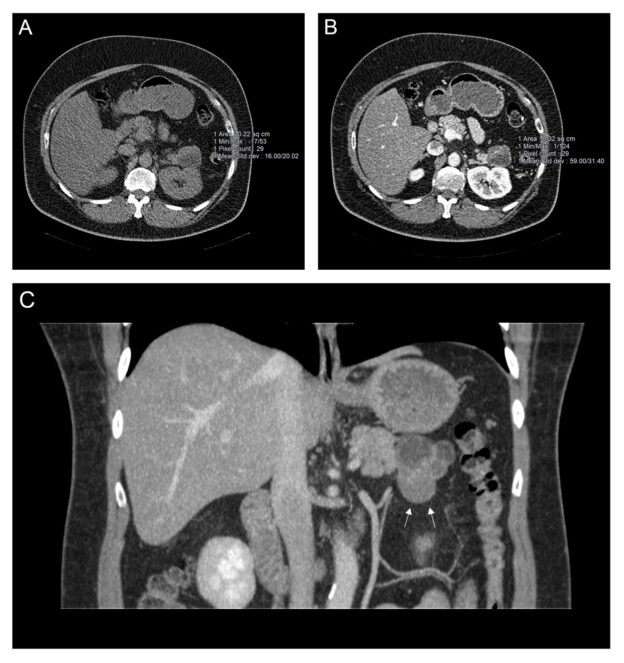

55-year-old man with exertional shortness of breath and palpitations

A 55-year-old man with a background history of Type 2 diabetes mellitus, hypertension, and dyslipidemia presented to a peripheral hospital with exertional shortness of breath and palpitations since COVID infection several months prior.